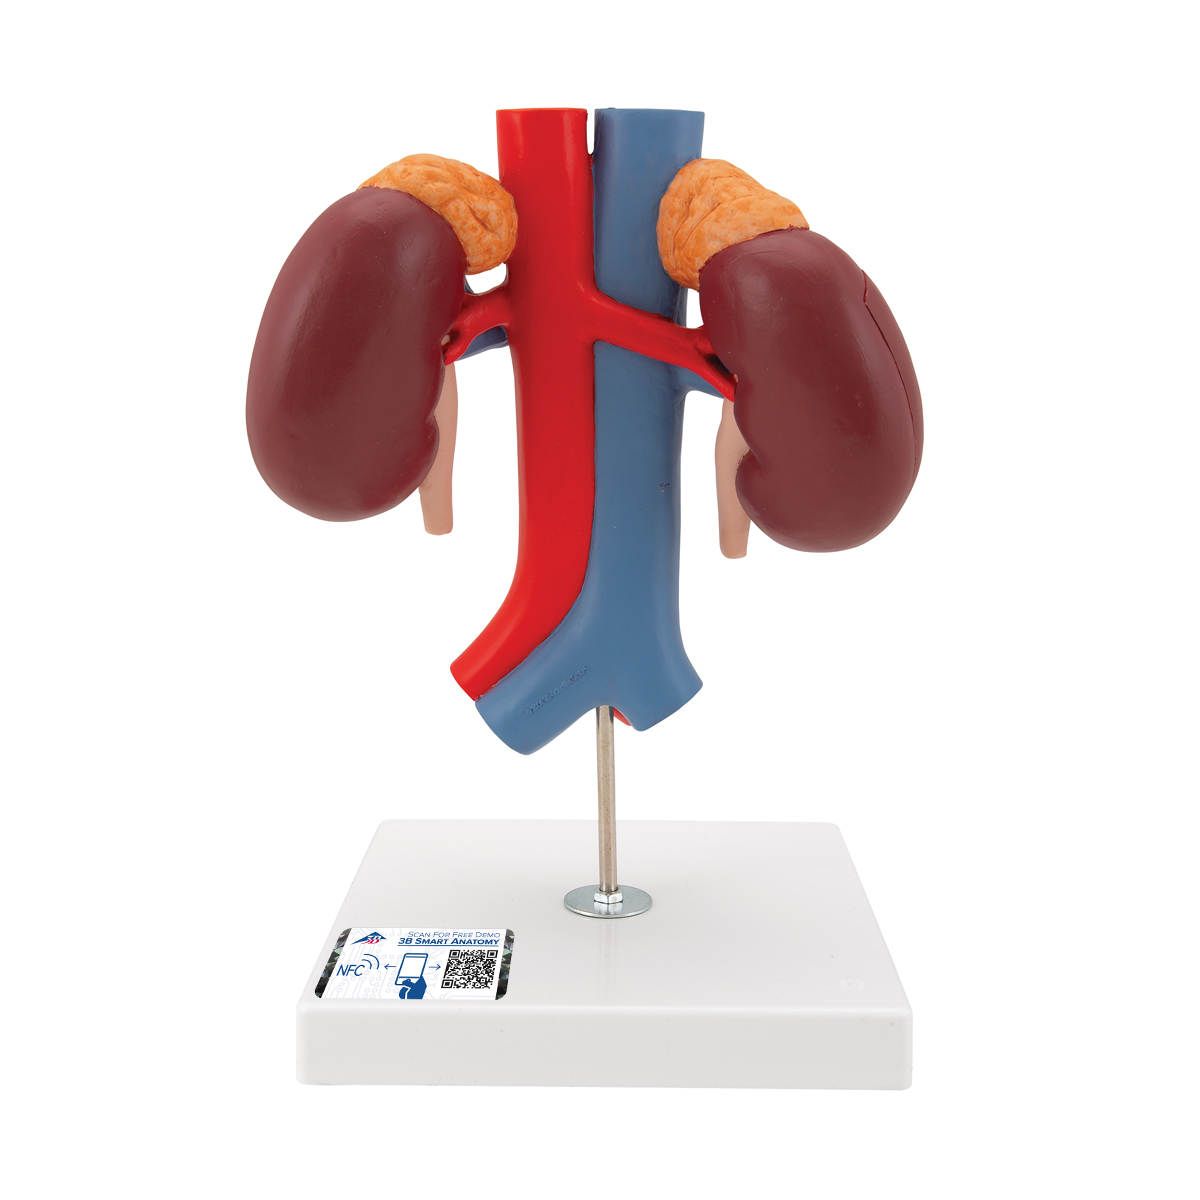

Эта модель в натуральную величину демонстрирует почки с надпочечниками, мочеточники, внутрипочечные сосуды и крупные кровеносные сосуды, расположенные в непосредственной близости от почек. Съемная передняя половина правой почки позволяет увидеть почечную лоханку, чашечки, корковый и мозговой слои почки. На подставке.